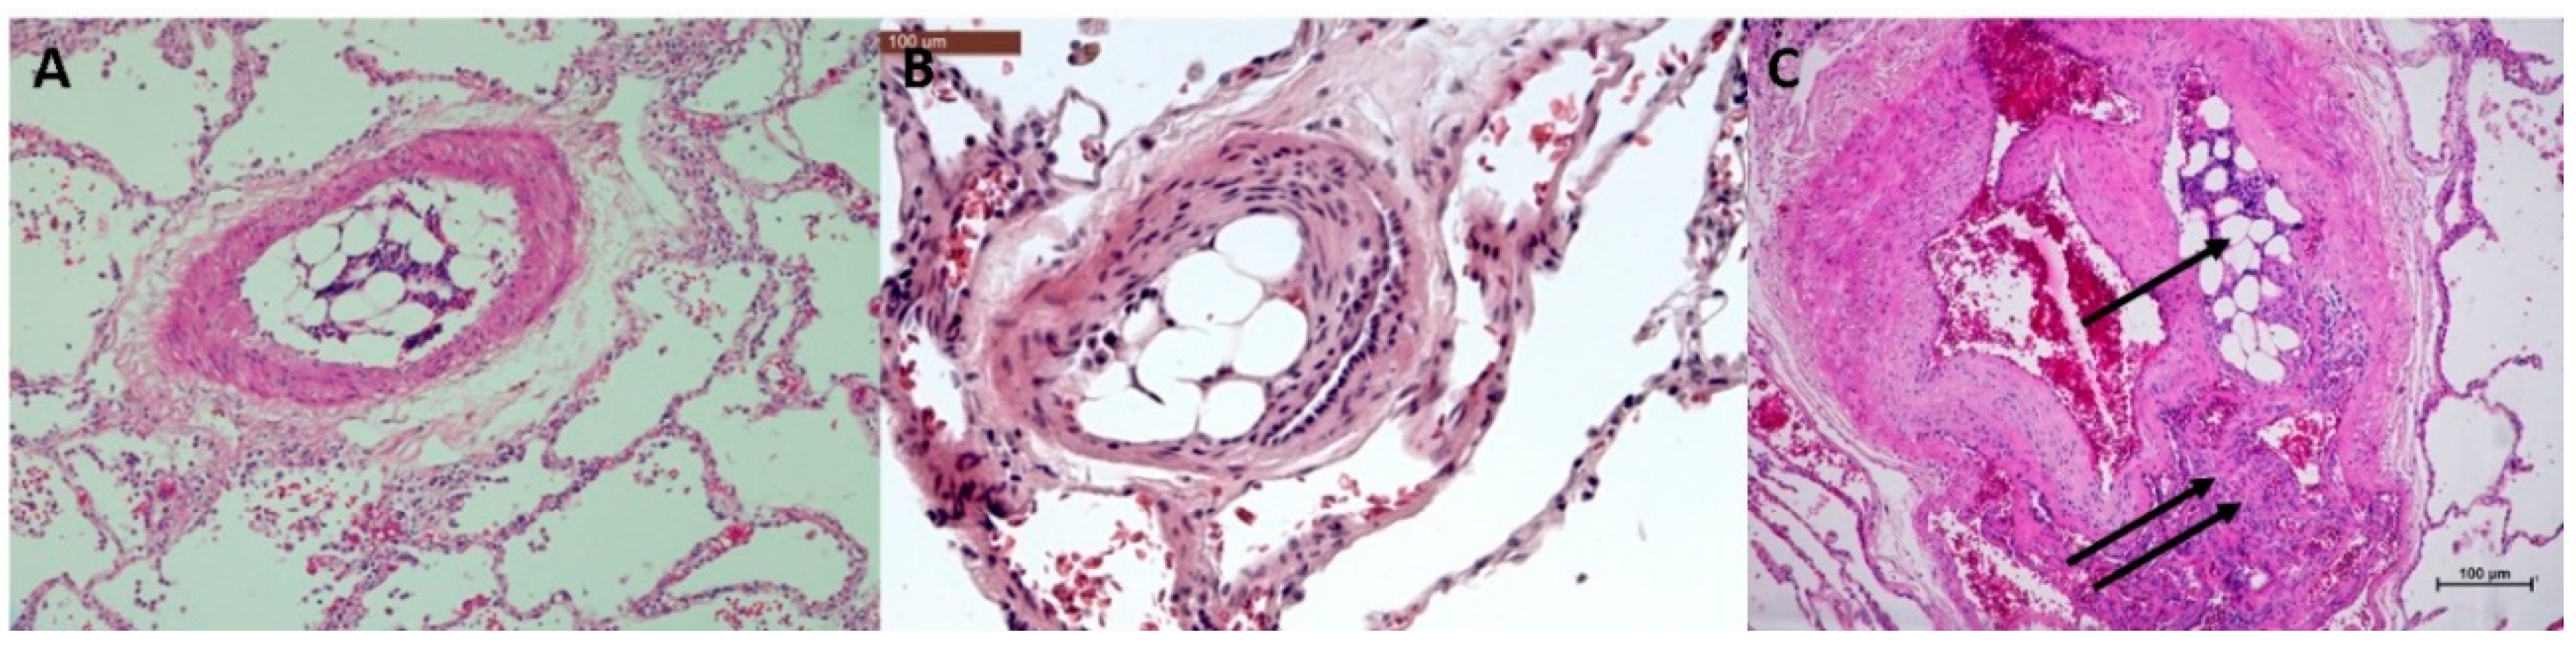

3.1. Histopathological Assessment of Angiophagy in Right Lower Lobes of the CTEPH Animal Model

3.2. Quantitative Morphological Analysis of Angiophagy in Right Lower Lobes of the CTEPH Animal Model